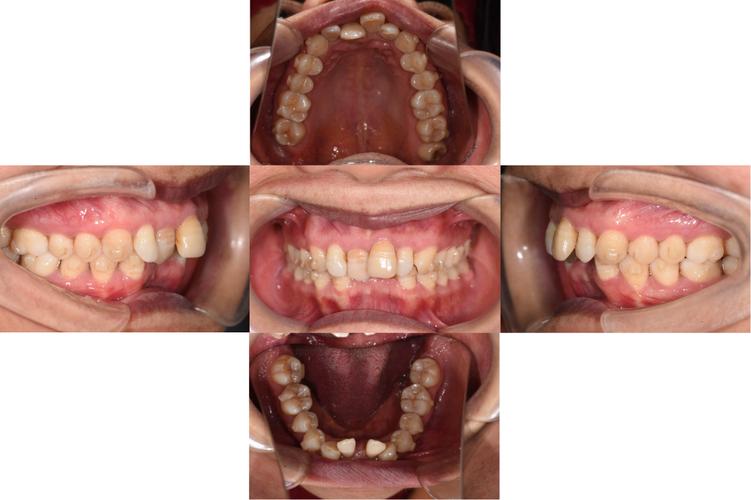

- 牙周病继发错颌畸形者:因牙周支持组织破坏导致牙齿移位(如扇形移位、唇倾、伸长)、牙间隙增大、咬合创伤(如早接触、干扰)等,影响咀嚼功能或美观。

- 正畸需求伴牙周风险者:成人患者存在错颌畸形(如牙列拥挤、深覆颌、深覆盖),同时伴有局部或全身牙周危险因素(如糖尿病、吸烟、口腔卫生不良),需先改善牙周条件再启动正畸。

- 疗效评估:治疗3-6个月后复查,牙周袋深度≤3mm,探诊出血(BOP)率<20%,牙齿松动度≤Ⅰ度,无牙周脓肿等急性症状,方可进入正畸阶段。

正畸过程中需兼顾牙齿移动效率与牙周安全,避免“重力学、轻生物学”的误区。

- 牙周监控:正畸期间每4-6周复查1次,包括牙周探诊(袋深度、附着丧失)、牙龈炎症指数(GI)、牙根尖片(观察牙槽骨改建情况);若出现牙龈增生、牙周袋加深,需暂停加力,先行牙周治疗。